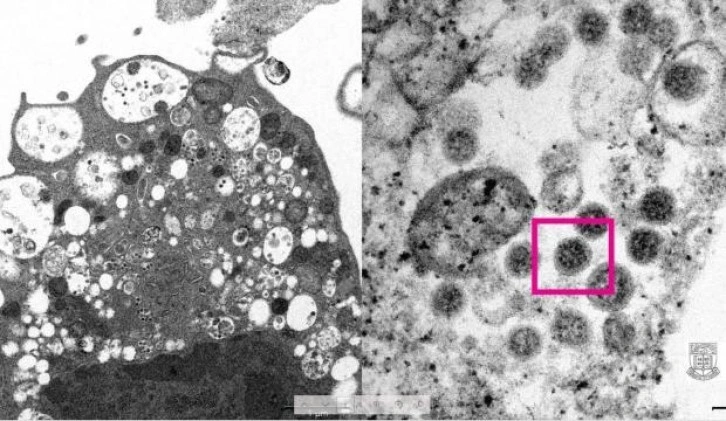

Hong Kong Üniversitesi Li Ka Shing Tıp Fakültesi (HKUMed) tarafından yapılan açıklamada, araştırmacılar tarafından SARS-CoV-2 virüsünün Omicron varyantının elektron mikroskobu görüntüsünün ortaya çıkarıldığı belirtildi.

Üniversite tarafından yayınlanan fotoğrafın solunda, küçük siyah viral partiküller içeren şişmiş veziküllerle hücre hasarını gösteren, SARS-CoV-2 Omicron varyantı ile enfeksiyondan sonra bir maymun böbrek hücresinin (Vero E6) düşük büyütmeli elektron mikrografının yer aldığı ifade edildi. Fotoğrafın sağında ise yüzeylerinde korona şekilli sivri uçlara sahip viral partikül kümelerini gösteren enfekte bir Vero E6 hücresinin yüksek büyütmeli elektron mikrografının yer aldığı belirtildi.